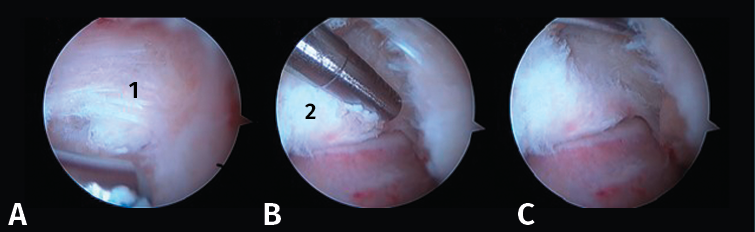

Figura 4. A: imagen artroscópica que muestra el ligamento peroneo-astragalino posterior (LPAP) (1); B: resección del LPAP con un sinoviotomo orientado medialmente contra la cara lateral del proceso posterolateral del astrágalo (PPA) (2); C: cara lateral del PPA después de la resección del LPAP.

- Primer paso: retirar el LPAP, completamente en caso de PPAH y parcialmente en caso de OT. La resección del tejido ligamentoso se realiza apoyando la ventana del sinoviotomo contra el lateral del PPA (Figuras 4 A, B y C).

- Segundo paso: eliminar el tejido blando en la parte superior del PPA. La ventana del sinoviotomo se gira 90° para apoyarse sobre la parte superior del PPA. Con ello, se realiza la artrotomía tibioastragalina y se escinde la cápsula hipertrófica de la articulación posterior. Es importante realizar movimientos en plano horizontal para preservar la continuidad del ligamento intermaleolar y evitar una artrotomía de trazo vertical que podría seccionar inadvertidamente dicho ligamento (Figuras 5 A, B y C).